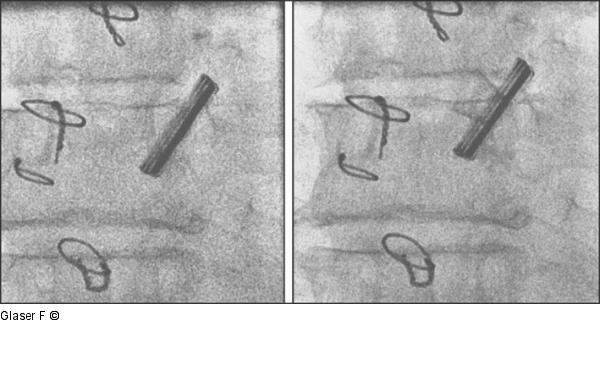

Abbildung 9: Durchleuchtung Projektion Durchleuchtung RAO 10°, Seitenansicht der Prothese: eindeutig freies Klappenspiel. |

Durchleuchtung RAO 10°, Seitenansicht der Prothese: eindeutig freies Klappenspiel. |